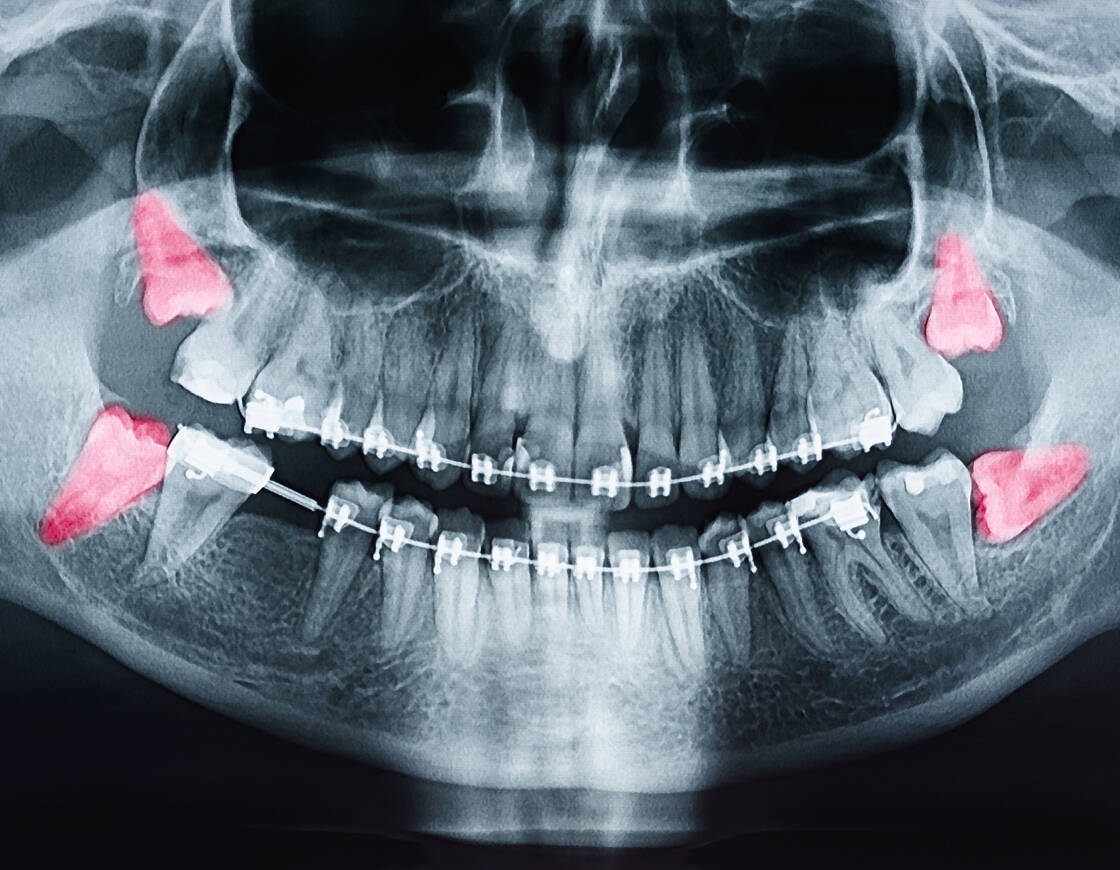

即日抜歯を控えるケース

-

親知らずの状態

親知らずが横向きに生えていたり、歯茎や骨に埋まっている場合は、周囲の歯や神経、骨の状態を正確に把握するため、レントゲン検査やCT撮影を行い、検査後、別日の抜歯をご提案する場合がございます。

事前の詳細な診断

最先端の診断機器を用いて、事前に詳細な診断を行い、患者さま一人ひとりに最適な治療計画を立てます。

診察・カウンセリング

レントゲンやCT撮影を行い、親知らずの位置や状態を確認します。